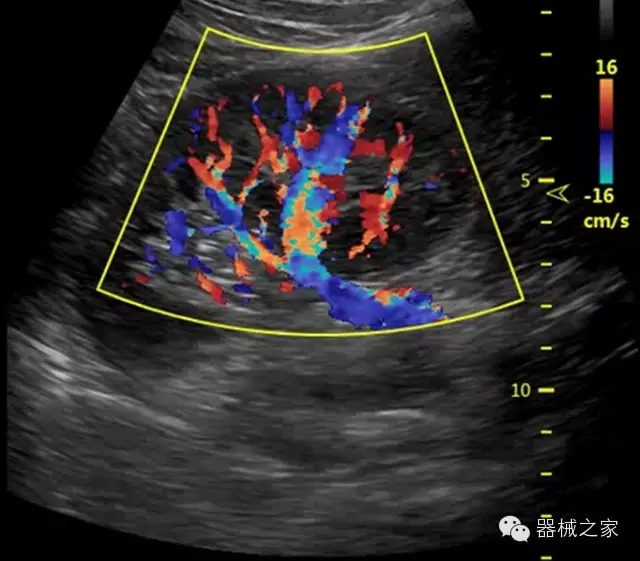

臨床圖片賞析

·獨(dú)有的RF平臺(tái)提高微小細(xì)節(jié)顯示、圖像對比度和邊界清晰度;

·特有的XCEN探頭,超寬的帶寬,表現(xiàn)更高分辨率和對比度;

·單晶純凈波探頭提供更佳的穿透力和彩色敏感度;

·完整的3D/4D臨床應(yīng)用,STIC, MCUT 和Auto NT等滿足產(chǎn)科所有應(yīng)用;

·更高的HQ羊膜腔鏡成像技術(shù)精細(xì)觀察每一個(gè)暗區(qū)細(xì)節(jié);

·飛依諾特有心臟純凈波探頭提供更好的穿透力和彩色敏感度,以及結(jié)合TView梯形拓展改善困難病人深部組織成像;

·獨(dú)有RF敏感血流使得心臟血流完美呈現(xiàn);